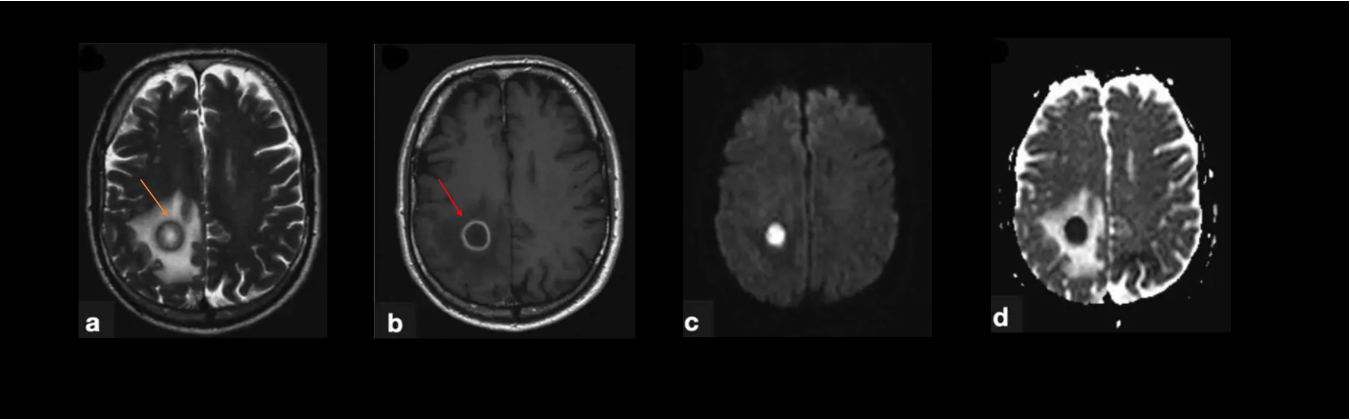

EBV antigen titers were quantified in a cohort of 37 pwRIS, 50 people with MS (pwMS), and 24 healthy controls (HC) using Enzyme-Linked Immunosorbent Assay (ELISA). Cognitive function of pwRIS were assessed using Minimal Assessment of Cognitive Function in Multiple Sclerosis (MACFIMS).

Anti-EBV Antibody Responses Across MS Subtypes and RIS

Figure 1

Figure 1. Anti-EBV antibody titers in HC, pwRIS, relapsing-remitting MS (pwRRMS), and primary progressive MS (pwPPMS). (A) Viral capsid antigen (VCA) IgG titers and (B) Epstein–Barr nuclear antigen 1 (EBNA1) IgG titers were measured by ELISA. *p < 0.05 with Mann-Whitney U test.

Anti-EBV Antibody Titers in Relation to Global Impairment

Figure 3

Figure 2. Anti-EBV antibody titers in patients with or without global impairment. (A) VCA IgG titers and (B) EBNA1 IgG titers measured by ELISA. *p < 0.05 with Mann-Whitney U test.

Association Between EBV Antibody Levels and Cognitive Function

Figure 4 1

Figure 3. Correlation of EBNA1 IgG Titers with Minimal Assessment of Cognitive Function in Multiple Sclerosis (MACFIMS) Scores. Scatter plots showing the correlation between EBNA1 IgG titers and Z-scores from (A) Brief Visuospatial Memory Test (BVMT), (B) California Verbal Learning Test (CVLT), (C) Judgment of Line Orientation (JOLO), and (D) Symbol Digit Modalities Test (SDMT). The correlation coefficient (r) and p-values (P) were assessed using Spearman rank correlation.

Figure 4 2

Figure 3. (E–H) Scatter plots showing the correlation between EBNA1 IgG titers and Z-scores from (E) Paced Auditory Serial Addition Test 2-second version (PASAT2), (F) PASAT 3-second version (PASAT3), (G) Delis-Kaplan Executive Function System - Color-Word Interference Test: Condition 3 (DKEFS CS), and (H) DKEFS - Design Fluency: Condition 1 (DKEFS DS). The correlations were assessed using Spearman rank correlation.

Conclusions

Elevated EBNA1 titers are detectable prior to MS symptom onset and are associated with cognitive function of pwRIS. However, their role in disease progression and clinical outcomes require further investigation.